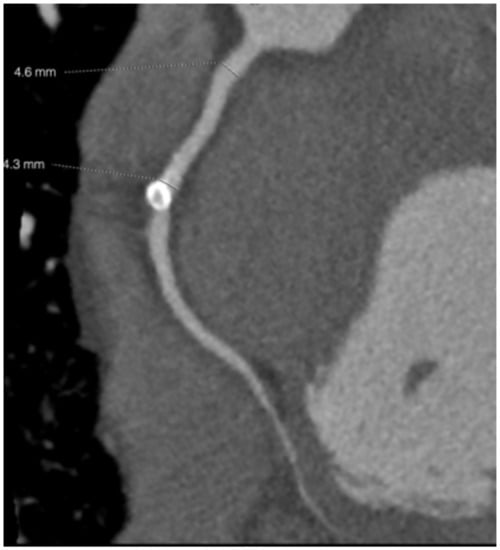

Major Complication Following Kawasaki Disease in an Infant—The Development of Apical Infarction and Aneurysm Formation

2. Case Report